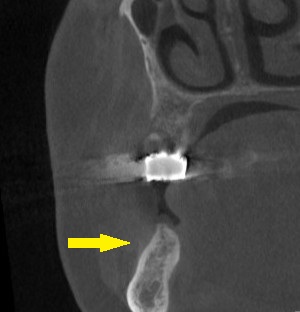

ご了承いただけましたので、本日、2本のインプラント埋入と、骨造成術を行いました。

下の写真3段目が手術後のCTです。